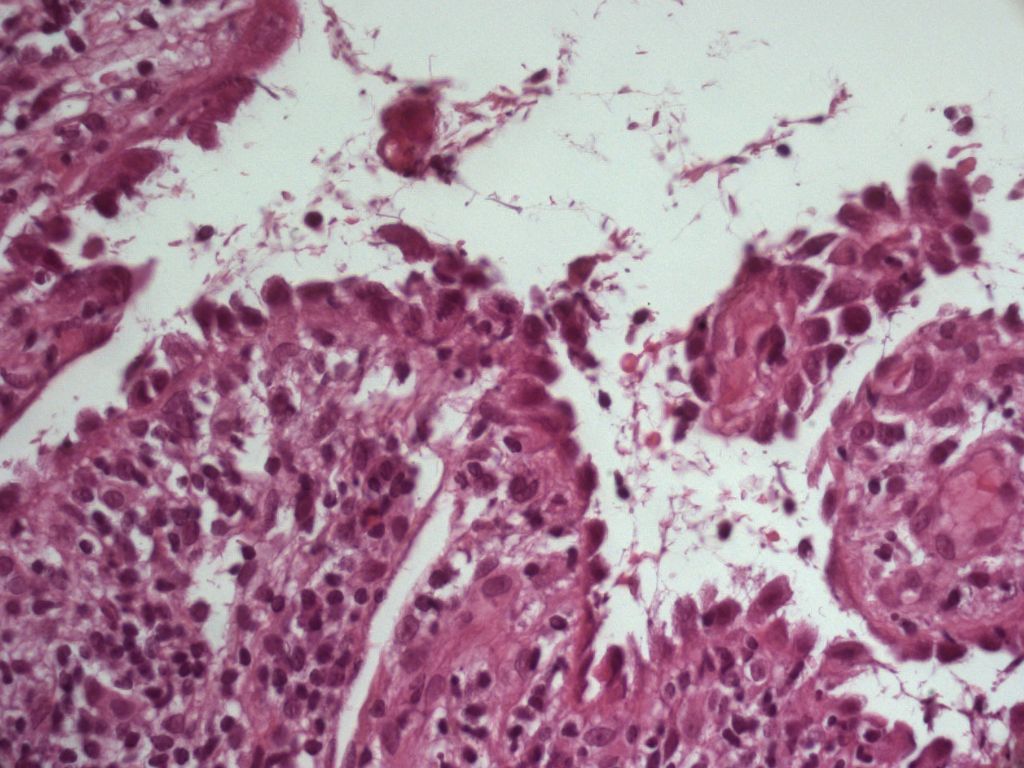

PA sarcoom |

PA: intra-epidermale bulla, acantholyse onderste lagen

epidermis. DIF: IgG intercellulair in visnetpatroon zoals bij pemphigus, soms

echter tevens IgG en C3 rond basaalmembraanzone. IIF (serum): circulerende antistoffen

tegen esophagusepitheel maar ook tegen blaasepitheel, die met immunoprecipitatietechnieken

verder kunnen worden uitgesplitst (indien lokaal niet beschikbaar, neem contact

op met Dermatologie Groningen). Antistoffen correleren met ziekte activiteit.